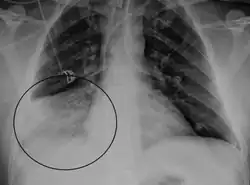

Frontal chest radiograph of a 47-year-old with encephalitis-associated human metapneumovirus. Consolidation in the right middle lobe (circle) indicating pneumonia.